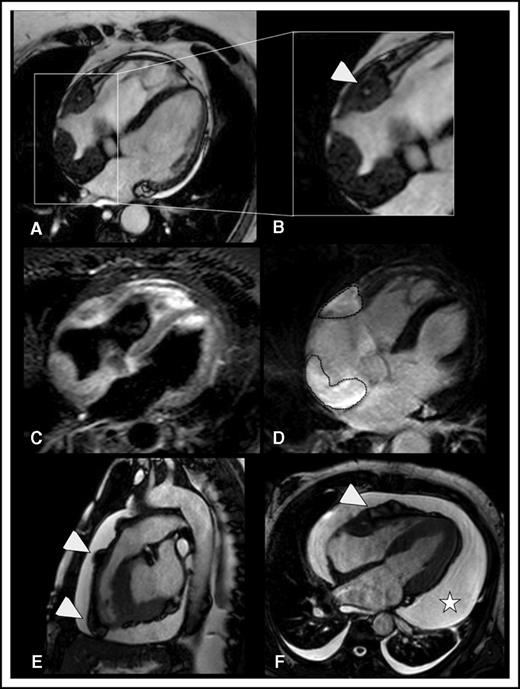

Twenty patients (87%) were men; the median age at diagnosis was 48 years (range 22-72). Fourteen patients (61%) had traditional cardiovascular risk factors (eg, diabetes, dyslipidemia), and 5 patients had overt cardiovascular disease (eg, coronary artery disease, peripheral arterial disease, atherosclerotic aortic aneurysm) prior to ECD diagnosis (supplemental Table 1, available on the Blood Web site). Table 1 illustrates the main sites involved by the disease. Ten patients (43%) had MRI evidence of cardiac involvement, with myocardial involvement in 9 and pericardial involvement in 9. Six patients had thoracic large-vessel involvement together with cardiac lesions, whereas only 1 patient had thoracic aorta involvement without cardiac disease (Table 1). MRI revealed peculiar patterns of myocardial involvement (Figure 1): most patients with cardiac disease had right atrial involvement, usually in the form of an atrial pseudotumoral mass, mainly involving the posterior atrial wall and often protruding into the atrium; another common lesion was the infiltration of the right atrioventricular sulcus, where the tissue usually surrounded or infiltrated the right coronary artery. However, none of the 7 patients with right pericoronary infiltration had ECD-related ischemic cardiac lesions. Unlike other infiltrative disorders, ECD did not cause diffuse infiltration of the myocardium, a finding in line with the usually normal systolic or diastolic functions observed by MRI or echocardiography (Table 1; supplemental Table 1; supplemental Video 1). Pericardial infiltration/thickening was common, often accompanied by pericardial effusion (Figure 1; supplemental Video 1) leading to tamponade in 2 cases and requiring pericardiocentesis in 3 cases. Unlike in other reports,2 we found no MRI evidence of ECD-related valvular disease. Thoracic large-artery involvement was generally characterized by perivascular thickening of the thoracic aorta and the origin of the epiaortic arteries (supplemental Figure 1), but no luminal narrowing or aneurysms were detected.

Myocardial and pericardial involvement in ECD. (A-D) Myocardial lesions. ECD typically affects the myocardium by infiltrating the posterior wall of the right atrium, forming soft tissue density masses with smooth surface, which appear hypointense in b-SSFP sequences (the lesions are framed in A). This b-SSFP hypointense infiltration also develops in the right atrioventricular groove, where it encases the right coronary artery (arrowhead in B). T2w image with signal fat suppression shows that there might be diffuse slight hyperintensity within the soft tissue, which usually corresponds to edema (C). In inversion recovery T1w sequences, late enhancement of the lesional soft tissue likely reflects disease activity/inflammation (dotted lines in D). (E-F) Pericardial lesions. ECD-related infiltration of the pericardium causes soft tissue density nodules arising from the visceral pericardial sheets, in association with pericardial effusion. b-SSFP sequences (E-F) allow optimal visualization of the nodules that appear hypointense as compared with the hyperintense pericardial effusion. Arrowheads indicate soft tissue pericardial nodules in the right ventricle outflow tract (E) and right ventricle free wall (F). The pericardial nodules are associated with conspicuous circumferential pericardial effusion (star in F). (A-D,F) Four-chamber view (a plane that allows comprehensive evaluation of myocardium and pericardium). (E) Sagittal view (the best plane to depict the right ventricle ouflow tract).